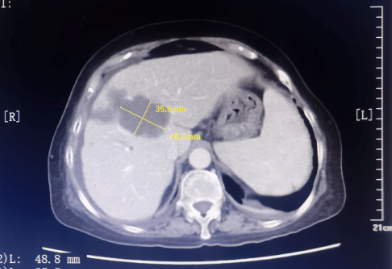

患者为67岁女性,1年余前诊断胃腺癌晚期,肝脏、骨骼及淋巴结多发转移,本次入院复查发现肝脏病灶进展,科主任白俊主任医师、主管医生刘莹主治医师详细分析并与患者家属沟通病情,考虑患者既往接受多线系统性抗肿瘤药物治疗,且治疗过程中多次出现剂量限制性骨髓毒性,继续更换药物治疗的选择空间不多,推荐超声引导下微波消融部分肝脏转移病灶,以期为后续继续免疫及靶向治疗创造在体瘤苗的机会。段宝军副主任医师认真阅片后,考虑该例患者肝转移病灶大(最大径超过5厘米),且毗邻膈肌、肝左静脉及第一肝门等重要结构,因此采用3D可视化手术规划系统设计微波消融方案,在麻醉科常建华副主任医师及手术室的精心配合下,顺利完成了肝转移病灶微波消融手术。